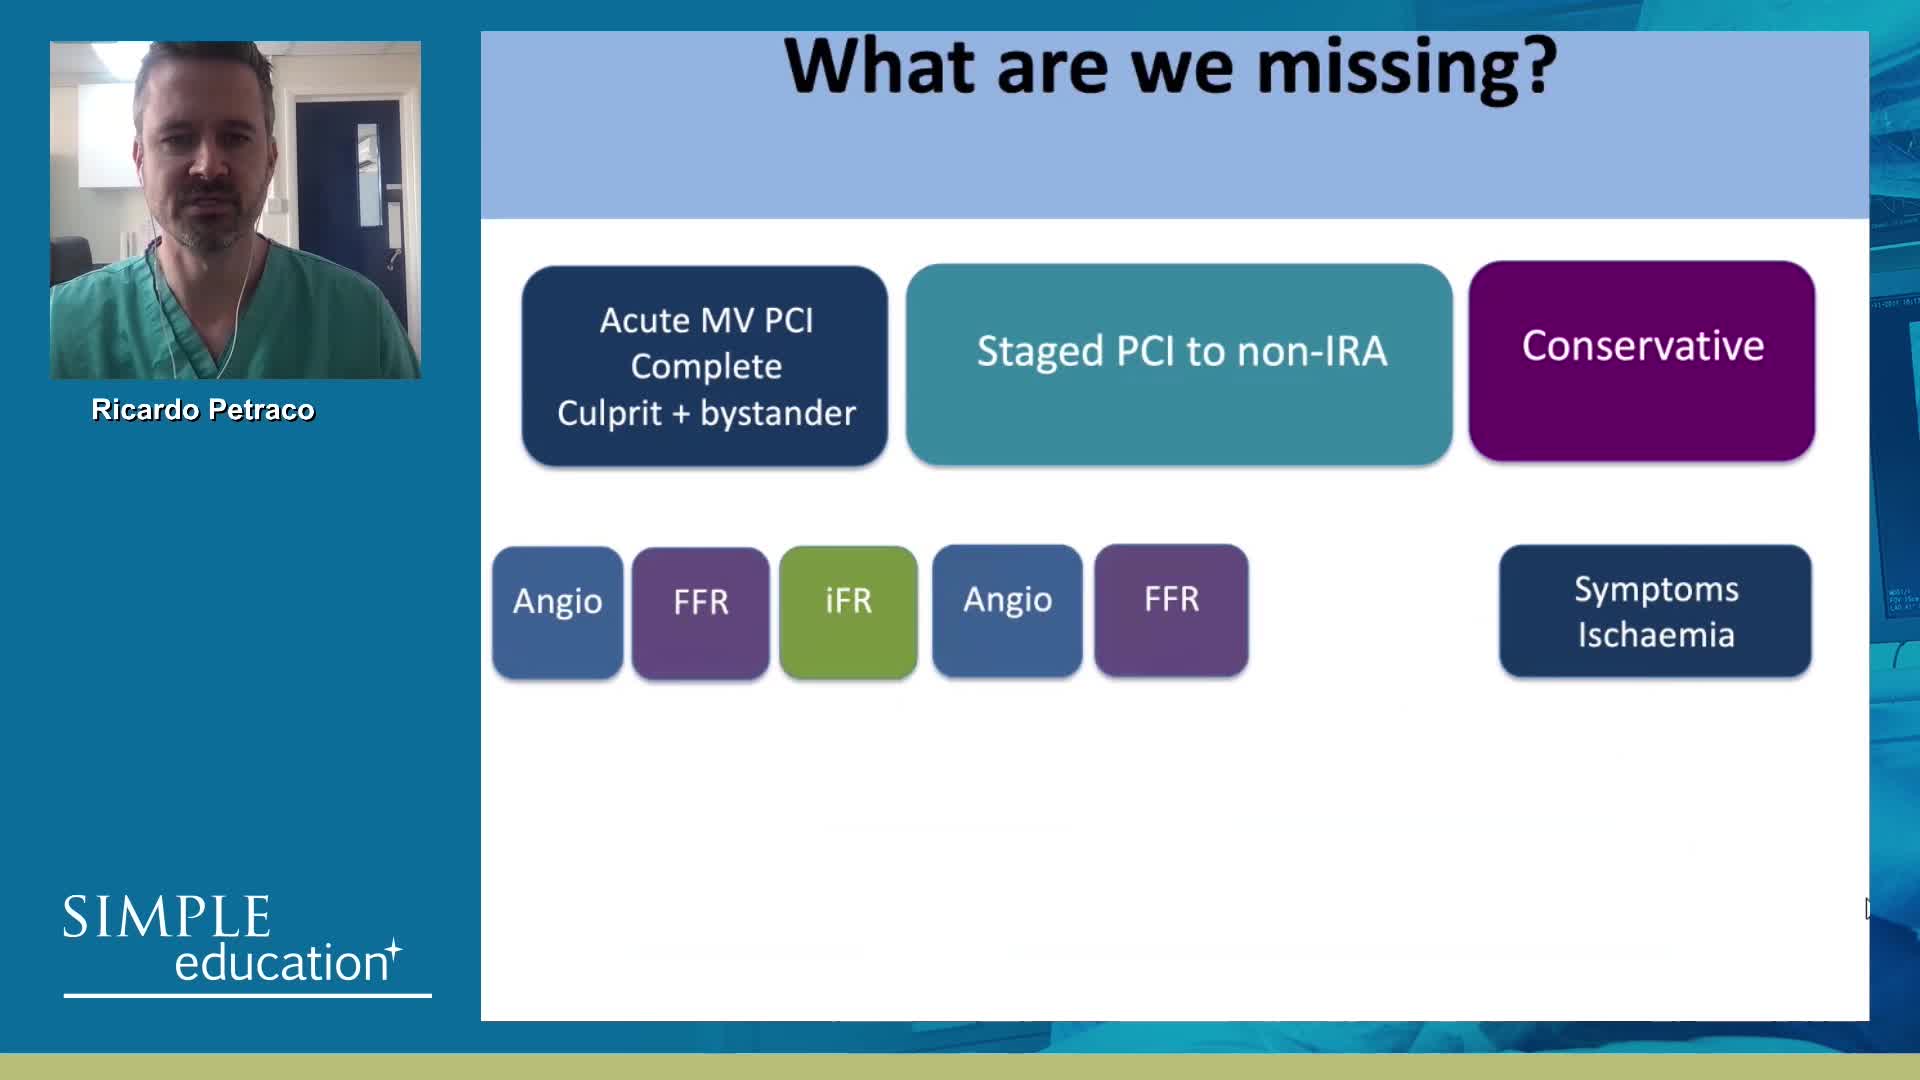

Breakout session: Common pitfalls of FFR and iFR assessment - Dr Ricardo Petraco

How to perform iFR and FFR, and best-practice measurement tips and tricks - Dr Ricardo Petraco

ABC for using Coronary Physiology in Aortic Stenosis, Primary Percutaneous Coronary Intervention (PPCI)/ACS, Muscle Bridges and Atrial Fibrillation - Dr Ricardo Petraco